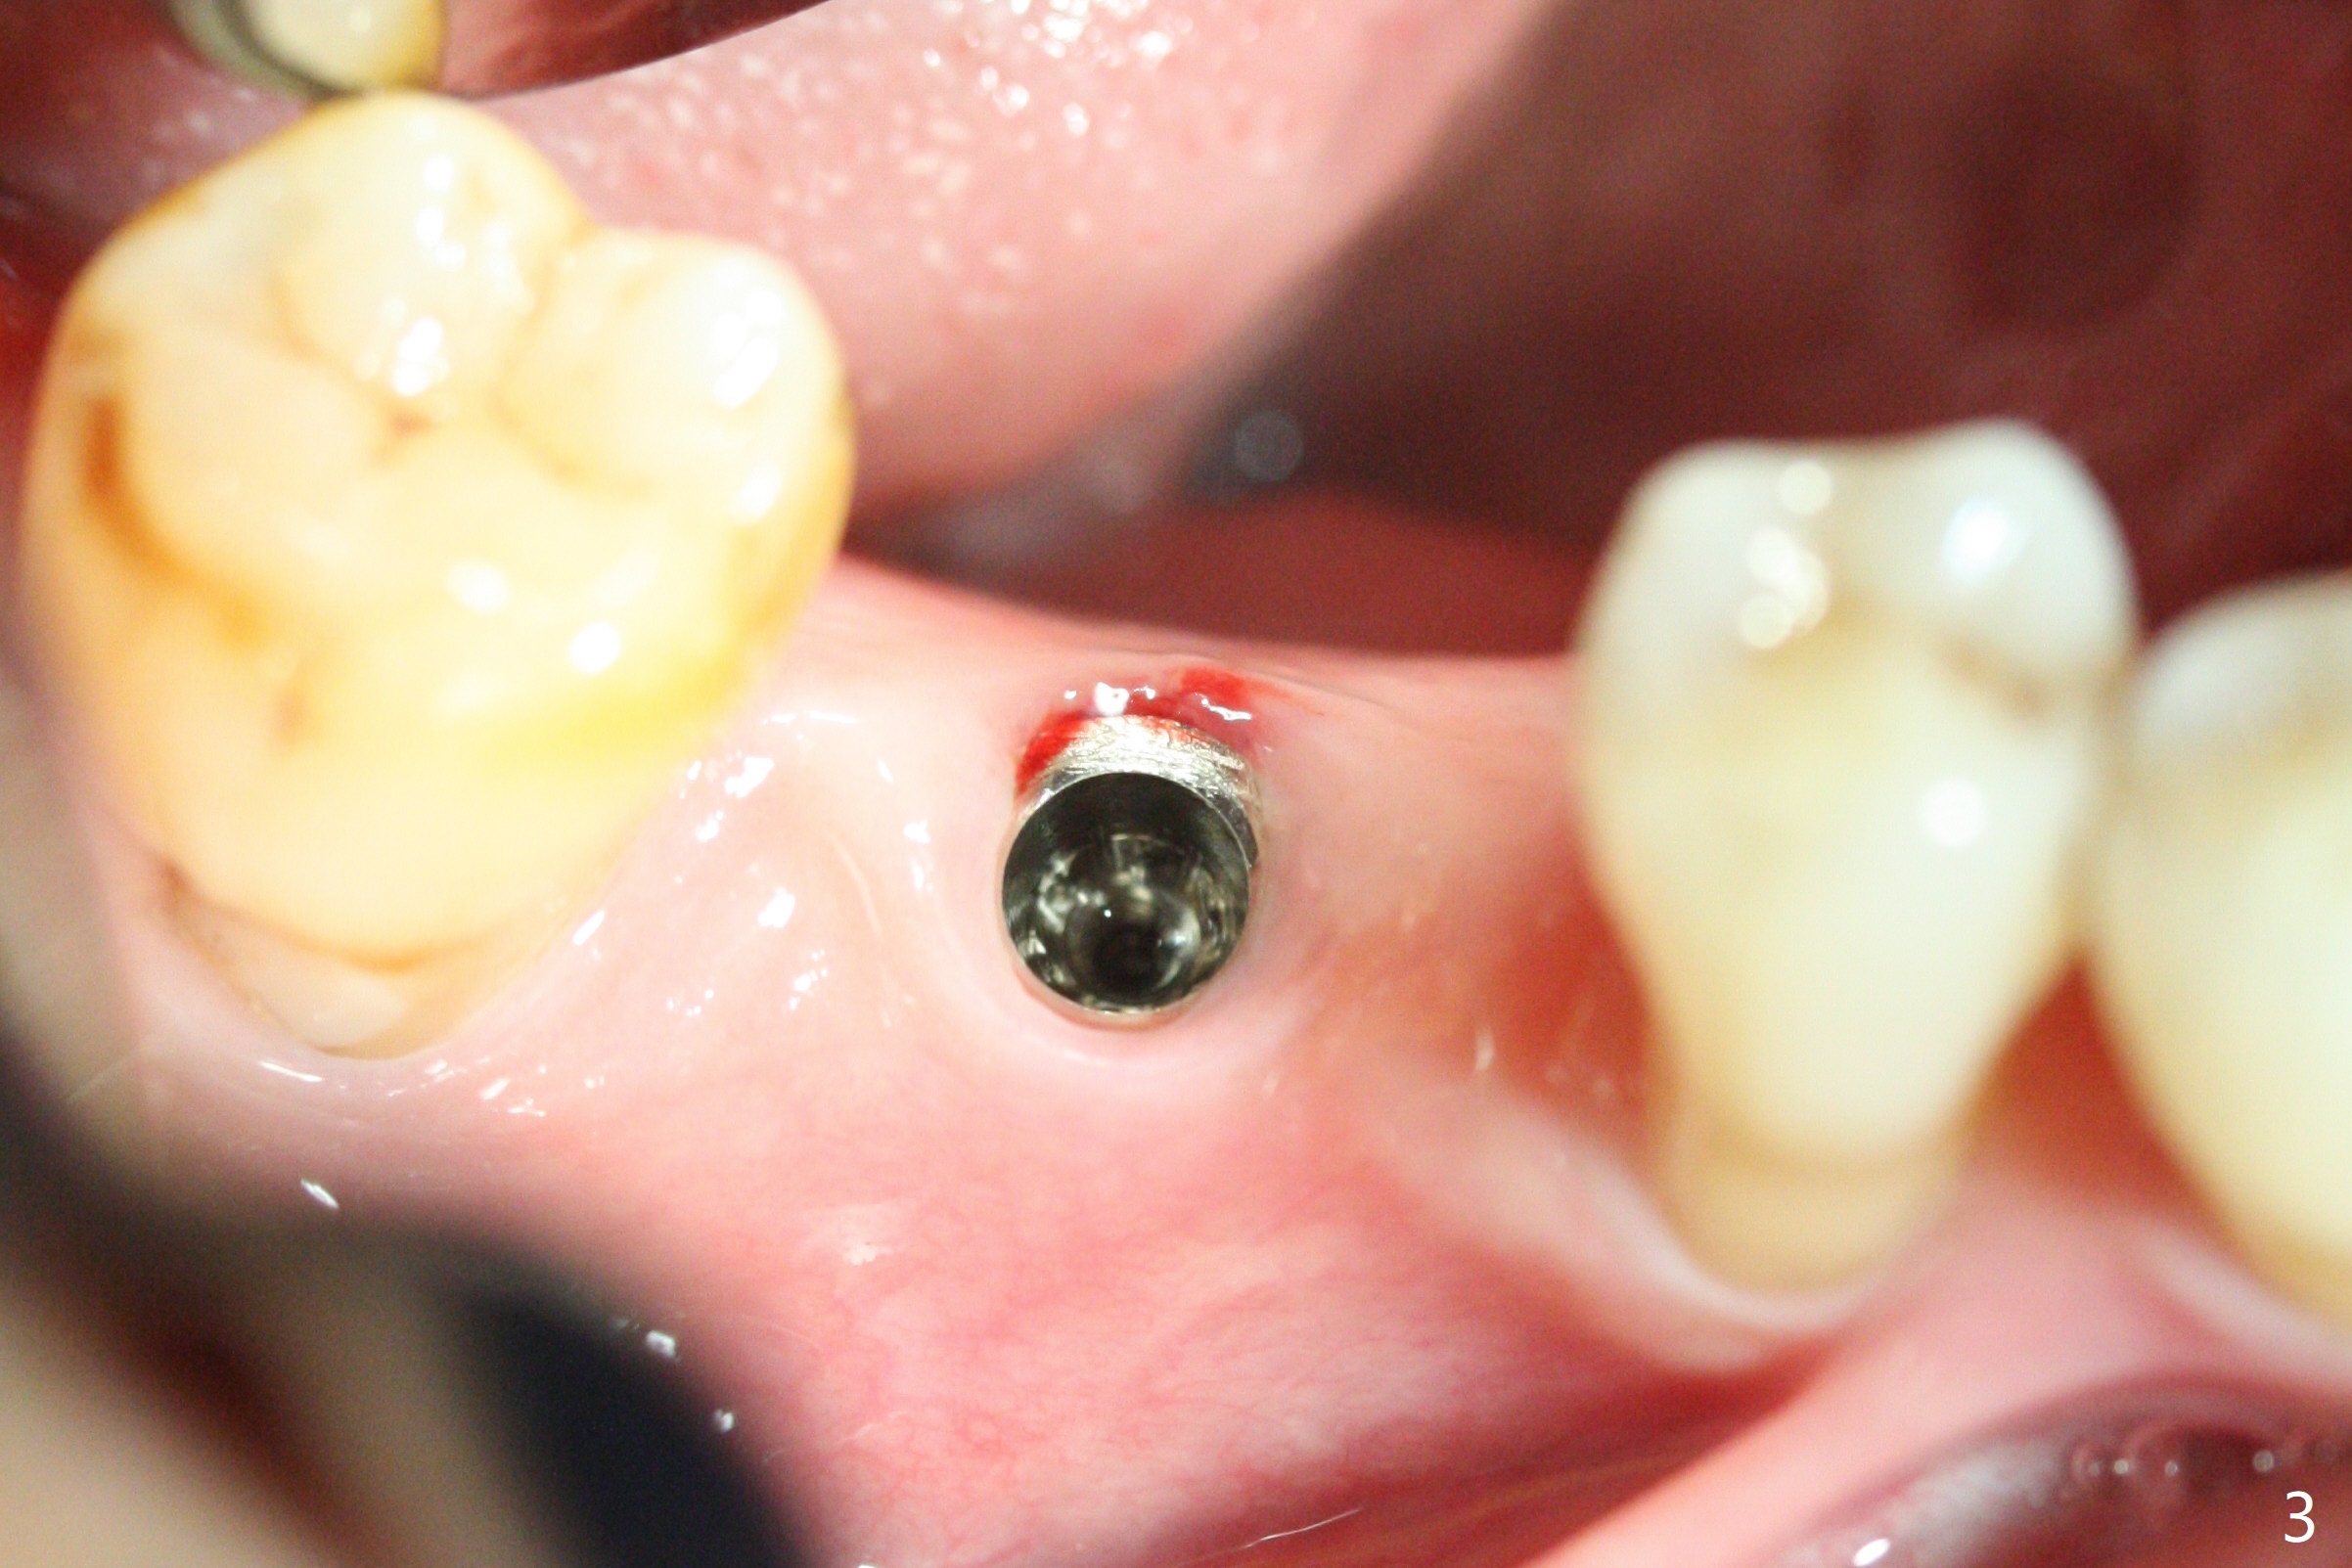

A 64-year-old man returns with history of a lump in the right submandibular region. Biopsy in a medical clinic shows inflammation. The implant crown at #30 has been cemented for ~ 4 years (Fig.1 (A: abutment)). The lingual plateau of the implant is exposed for 1-2 years asymptomatic (Fig.2 *). There is no deep lingual pocket when the crown and abutment are removed (Fig.3). Flap surgery confirms microthread exposure (circumferential, Fig.4). After removal of the microthreads with diamond bur (Fig.5), allograft (Fig.6 *), 6-month collagen membrane and a 6.5x5(3) mm healing abutment are placed. Following suturing, periodontal dressing is applied. The site remains asymptomatic 3 months postop, when an implant is placed subcrestal at #3.